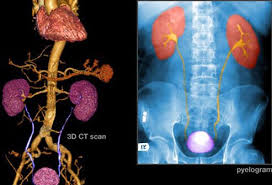

Bladder Cancer Cdc from www.cdc.gov Blood in urine (hematuria), which may cause urine to appear bright red or cola colored, though sometimes the urine appears normal and blood is detected on a lab test This is typically the first sign of bladder cancer. Stage 4 is the most advanced stage of cancer. The most common symptom of bladder cancer is blood in the urine. Here are the signs and symptoms of bladder and kidney cancer. Bladder and kidney cancers can occur independently of one another, but may appear at the same time if one type of cancer spreads to the other site. Kidney or bladder cancer can cause this symptom, but it could also be due to an. Around 80% to 90% of patients diagnosed with bladder cancer have this symptom.

Kidney cancer, on the other hand, involves the abnormal, uncontrollable growth of kidney cells.

The urine may look darker than usual, brownish, or. People with bladder cancer may experience the following symptoms or signs. The symptoms of stage 4 bladder cancer include tiredness, weakness, and pain. The bloody urine may be bright red, orange, or pink and occur regularly or intermittently. Here are the signs and symptoms of bladder and kidney cancer. Or, the cause of a symptom may be a different medical condition that is not cancer. Blood in the urine in most cases, blood in the urine (called hematuria) is the first sign of bladder cancer. Stage 4 is the most advanced stage of cancer. There may be enough blood to change the color of the urine to orange, pink, or, less often, dark red. Gross hematuria means you can see the blood in your urine, which may appear pink, red, or brownish in color. The urine may look orange or pink. The first sign of bladder cancer is usually blood in the urine. Bladder cancer is the 4 th most common cancer among veterans.